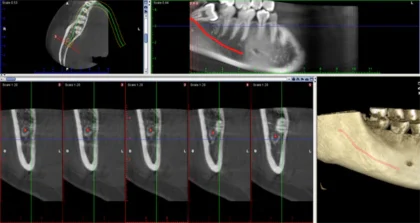

親知らずは横に傾いたり、埋まったまま出てこない場合が多く、手前の歯までむし歯になったり、歯ぐきが腫れたりしてトラブルの原因になってしまいます。親知らずはまっすぐ生えている場合には通常の抜歯で対応できますが、横向きに生えていたり、歯ぐきや骨に埋まっていたりする場合は、歯科口腔外科での処置が必要になります。当院ではCTを活用した精密な診断により、神経や血管の位置を把握したうえで、必要に応じて大学病院などの高度医療機関と連携しながら、安全性に配慮した抜歯を行います。

荻窪ツイン歯科・矯正歯科では、CTスキャンを用いて神経や血管の位置をしっかり確認したうえで、できるだけ痛みを抑えた処置を心がけています。症例によっては、大学病院などの専門機関をご紹介することも可能です。

CT撮影を行うことで神経と親知らずの位置関係を把握し、そのリスクを下げる事も可能です。